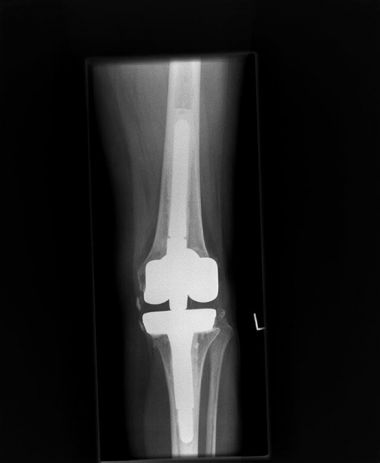

KNIEGELENKSENDOPROTHETIK

Durch jahrelange Arbeit mit künstlichem Kniegelenksersatz besitzen wir einen großen Erfahrungsschatz in diesem Bereich. Wenn das Kniegelenk durch den Gelenkverschleiß stark geschädigt ist und die Mobilität deutlich eingeschränkt wird, bietet der Ersatz des Kniegelenkes durch ein künstliches Gelenk eine erfolgversprechende Behandlungsmöglichkeit.

KNIEENDOPROTHESE

Ein künstliches Kniegelenk setzt sich zum einen aus einem glattpolierten Oberschenkelanteil, meist aus chirurgischem Stahl (Kerbstabilität), zum anderen aus einem flachen Schienbeinkopfteil aus Metall mit einem Zapfen zur Verankerung im Knochen des Schienbeinkopfes zusammen. Dazwischen wird ein Polyethylenstück eingesetzt, welches mit der Oberschenkelrolle das eigentliche Gelenk bildet. Im Falle einer Metallunverträglichkeit stehen spezielle Implantate zur Verfügung. Sprechen Sie uns an!

Bild flexion gap first Prothese

Die Bewegung des Kniegelenkes ist sehr komplex und wird durch die Bandstrukturen geführt. Die Bewegung basiert auf einer innenseitig eher stabil liegenden Rotationsachse und der Möglichkeit eines vermehrten Translationsspiels auf der Außenseite. In der Knieendoprothetik setzen wir eines der modernsten Knie Systeme am Markt (Stand 2022) ein. Das Implantatsystem bietet ein modernes Design, sehr feinabgestimmt mit Oberschenkelgrößen in 2 mm Schritten und Inlayhöhen in 1mm Schritten.

Durch den Gelenkverschleiß und die damit einhergehenden Veränderungen ist oft die knöcherne Formgebung des Gelenkes zum Operationszeitpunkt deutlich verändert und eignet sich nur bedingt als Referenzpunkt für die Positionierung von Implantaten. Wir bevorzugen daher eine weichteilbalancierte Technik, die auf der Schienbeinkopfseite die Operation beginnt.

Diese Technik (Flexion Gap First) ermöglicht es, die Bandspannung des Gelenkes sowohl für die Beugung als auch die Streckung innerhalb des Operationsfortgangs genau zu messen und so eine stabile Führung des Gelenks über das gesamte Bewegungsausmaß von der vollen Streckung bis in die Beugung zu erzielen.